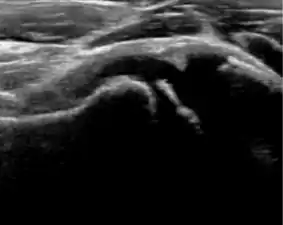

Ultrasound

Ultrasound is the first-choice technique for diagnosis of newborns hip dysplasia. In experienced hands with appropriate technology, ultrasound can also be useful during the first year of life. Some European healthcare systems encourage universal ultrasound screening in neonates between the sixth and eighth weeks. Although it shows higher initial costs caused, it leads to significant reduction in the total number and overall costs of dysplastic hips undergoing operative and nonoperative treatment.[1]

Ultrasound allows categorizing pediatric hips, according to Graf’s criteria, in four main types: normal, immature, and dysplastic (subluxed and dislocated). This classification is based on measurements of the acetabular inclination angle (alpha), cartilage roof angle (beta), and infant age. The femoral head coverage can also be determined by dividing the length of the femoral head covered by the acetabular fossa and the diameter of the femoral head. Its lower normal limits are 47% for boys and 44% for girls (Figure 11).[1]

Figure 11:

-

Useful ultrasound measures in neonatal hip sonography, alpha and beta angles.[1] -

Measurement of femoral head coverage.[1]

During childhood, ultrasound is a quick method to assess hip pain and quite often may be used to avoid use of irradiating techniques, such as radiography or CT. Ultrasound allows evaluation of joint effusion, synovial thickening and neovascularity, the bone/cartilage contour, and the femoral head-neck alignment. Although sonography is extremely sensitive in detecting increased synovial fluid, it is nonspecific and cannot be used with accuracy to determine the type of fluid. Transient synovitis of the hip, despite being the most frequent cause of pain in children between 3 and 10 years, remains a diagnosis of exclusion. It usually shows anechoic fluid, but echogenic fluid can also be found. The effusion is considered pathologic when it is measured at >2 mm in thickness. The differential diagnosis is wide, including osteomyelitis, septic arthritis, primary or metastatic lesions, LCPD, and SCFE. Discrimination from septic arthritis is challenging, often requiring joint aspiration. In septic arthritis, US is able to demonstrate a hip joint effusion, synovial thickening, and cartilage damage, although the appearances are nonspecific.[1]

A step between the head and the physis can be detected in children with SCFE, while abnormalities in the femoral head contour may suggest the presence of LCPD. In both cases, radiographs are mandatory to confirm diagnosis and severity (Figure 12).[1]

Figure 12:

Normal ultrasound appearance of the femoral head-neck junction. -

Joint effusion in transient synovitis of the hip. -

Flattening of the femoral head in a patient with Perthes disease. -

Step in the femoral head-neck junction in a patient with SCFE.